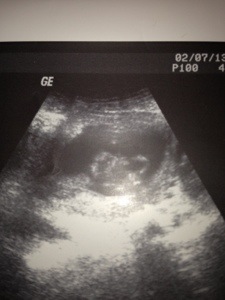

We had the opportunity to see #2 on ultrasound this Thursday! My OB had a tough time taking a picture because baby was jumping and flipping constantly! This is totally opposite from Siri, who couldn’t be convinced to move in ultrasound. We better prepare for a wild one!!

In this picture, baby is in profile facing right with one arm up and flexed toward its nose. 🙂